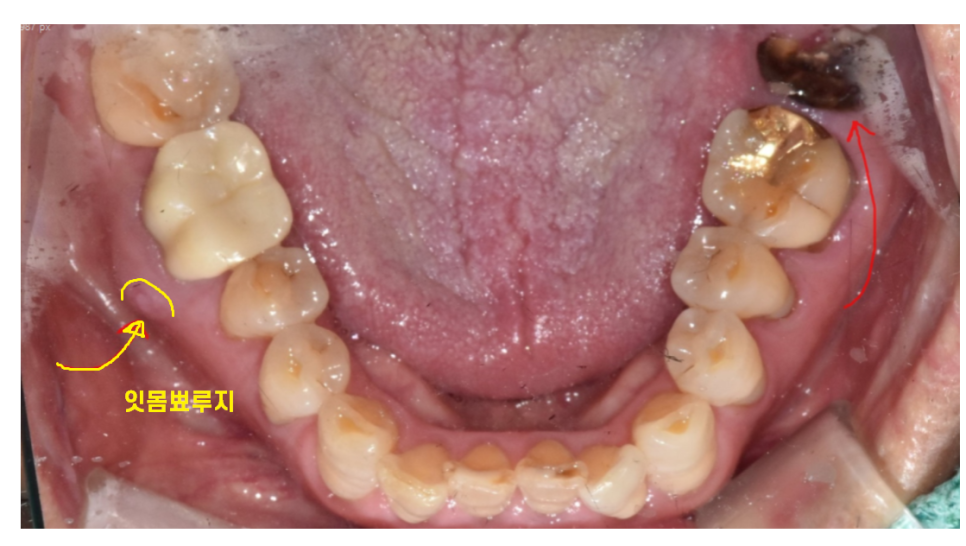

230214

아프지는 않다고 하셨지만

오른쪽 아래 어금니 치아도 염증이 있었습니다.

231029

이미 잇몸 밖으로 여드름 마냥

고름이 나오고 있었거든요ㅠㅠ